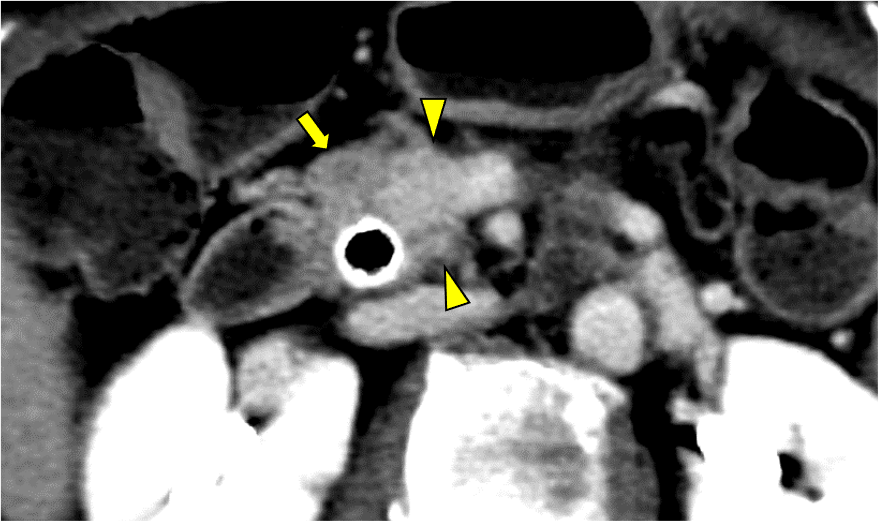

図3.造影CT 膵実質相 Axial像 70keV

膵頭部の膵癌病変(矢頭)は門脈 (矢印:黄)と半周を超える接触あり。上腸間膜動脈(矢印:赤)および、その他の主要な動脈との明らかな接触は認めなかった。

図4.造影CT 平衡相 Axial像 70keV

膵頭部の膵癌病変(矢頭)は平衡相では遷延性の造影効果がみられている。